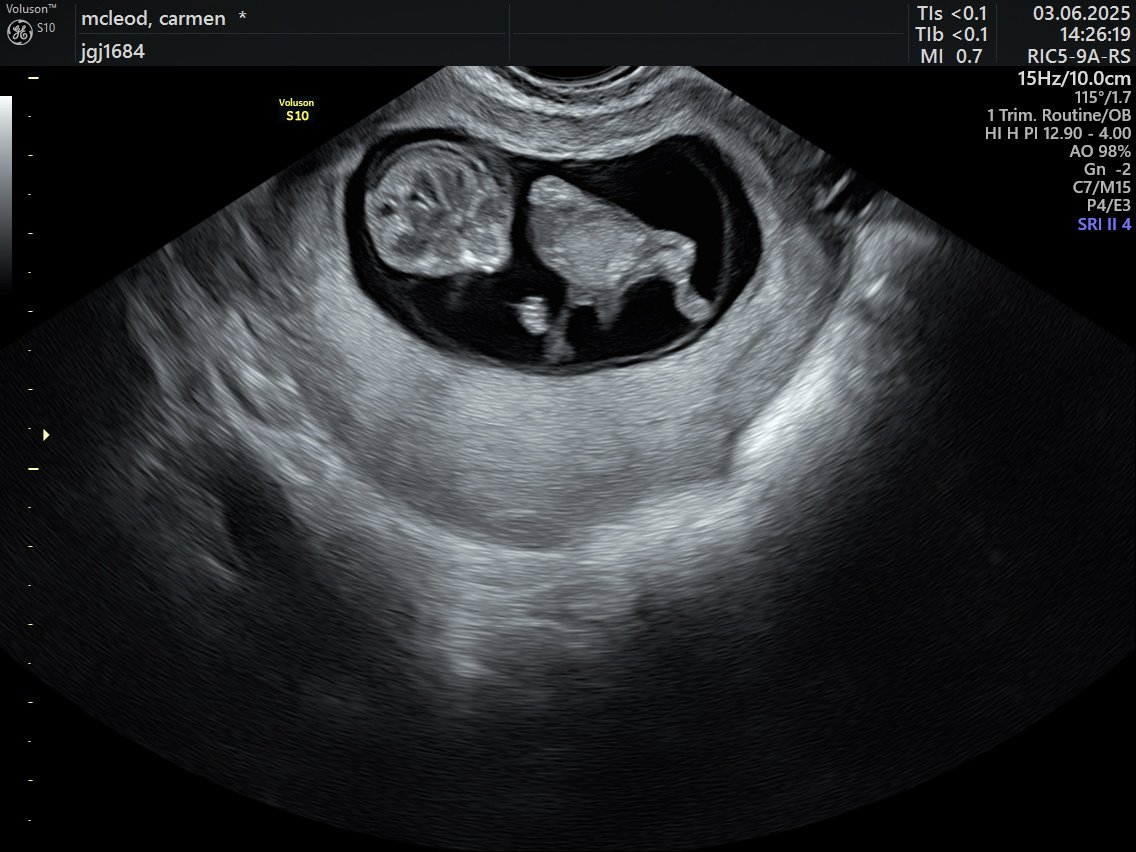

Little bean 🫘 due 23rd December ✨ got lucky and baby woke up during the sonar and wiggled around for us

Cjay tweet mediaCjay tweet mediaCjay tweet media